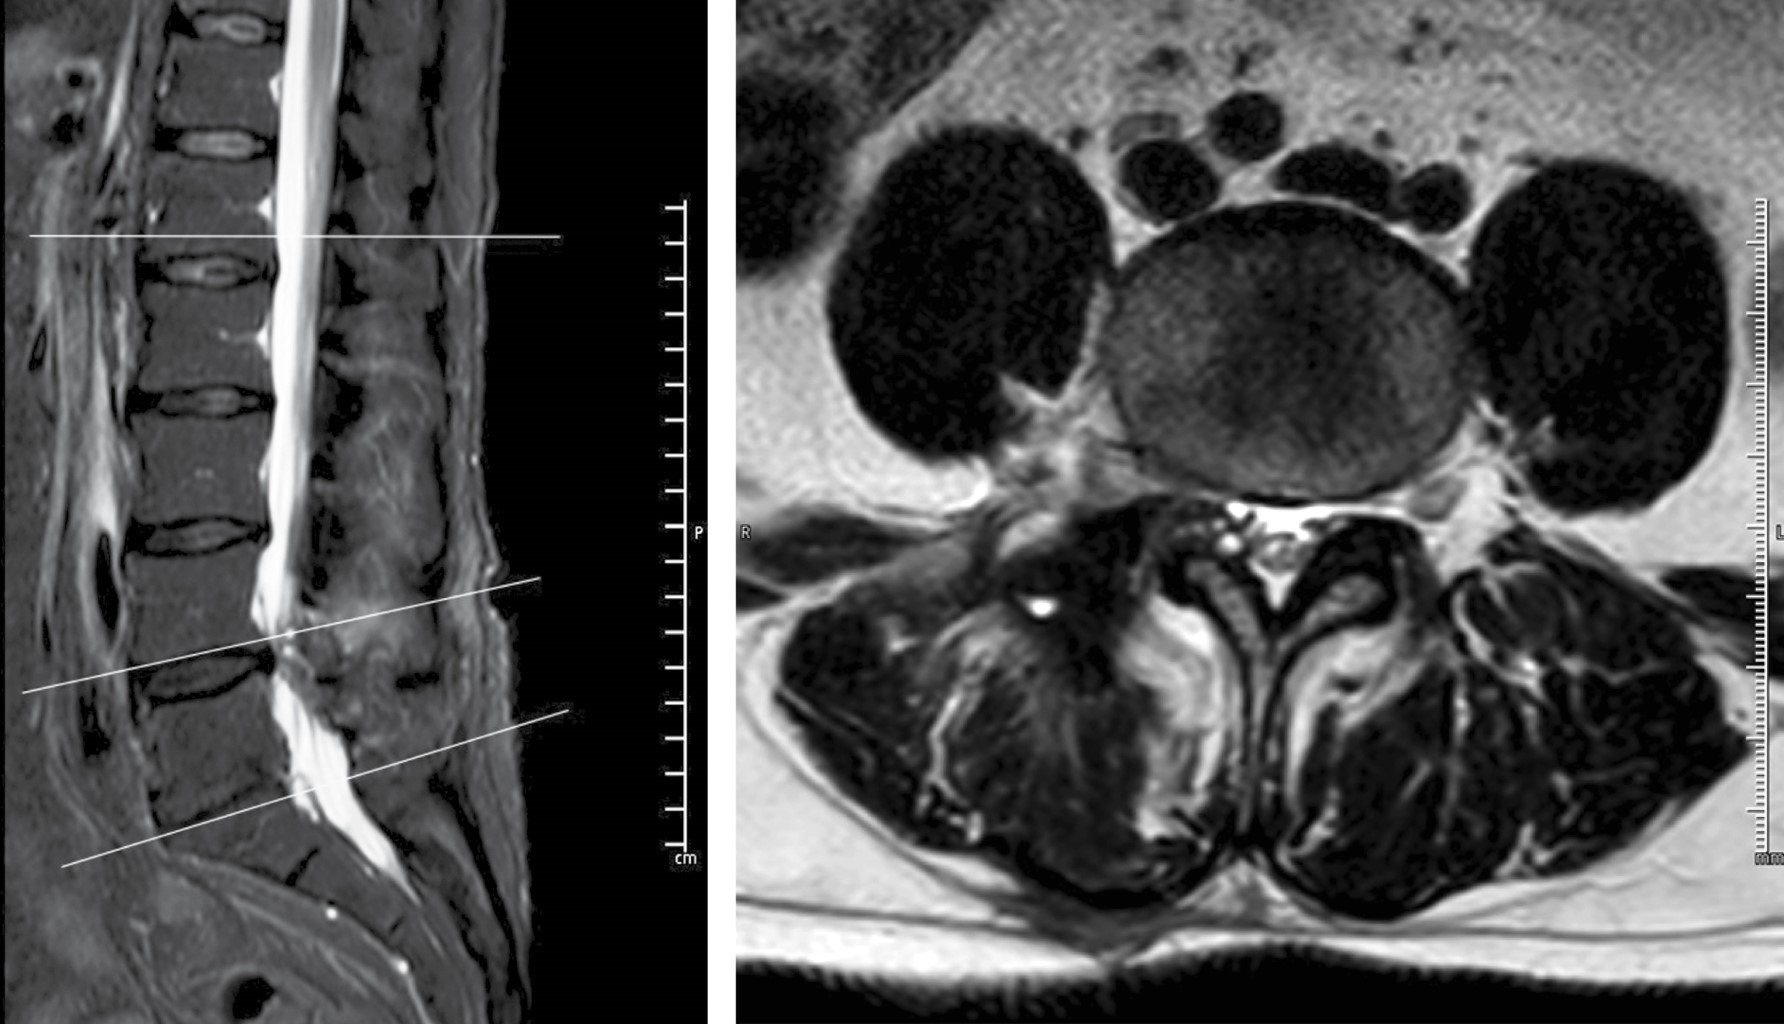

Después de realizar la microdiscectomía tubular, encontramos fragmento discal extraforaminal al igual que salida de material purulento (Figuras 3 y 4). Se tomaron muestras para cultivo, se realizó aseo quirúrgico y terminamos el procedimiento. El microorganismo aislado fue Staphylococcus aureus, por lo que se realizó interconsulta a infectología quien administró medicamento IV dirigido por antibiograma con ceftriaxona 2 gr IV cada 24 horas y daptomicina 500 mg IV cada 24 horas por seis semanas. Fue dado de alta a los cinco días después del procedimiento.

Los estudios de laboratorio en el postquirúrgico inmediato reportaron leucocitos de 14.8 × 103 cel/mm3 con 94% de neutrófilos, VSG de 54 mm/h y PCR 70 mg/l. El paciente reingresó para manejo del dolor en tres ocasiones, y en un estudio de imagen de seguimiento, con un mes de diferencia de la de ingreso, se evidenció la formación de abscesos paravertebrales (Figura 5). Posterior al tratamiento IV, se decidió continuar con trimetoprima/sulfametoxazol y doxiciclina por vía oral por dos meses más. El paciente respondió bien a la antibioticoterapia observando resolución de los abscesos en una nueva resonancia magnética dos meses después del inicio del tratamiento. Así mismo, durante sus reingresos y posterior a ellos, se estuvieron tomando estudios de laboratorio donde se evidenció disminución de los reactantes de fase aguda (PCR de 2.1 mg/l, VSG 26 mm/h).